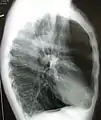

A chest X-ray is not useful to establish a diagnosis of COPD but it is of use in either excluding other conditions or including comorbidities such as pulmonary fibrosis and bronchiectasis. Characteristic signs of COPD on X-ray include hyperinflation (shown by a flattened diaphragm and an increased retrosternal air space) and lung hyperlucency.[5] A saber-sheath trachea may also be shown that is indicative of COPD.[111]